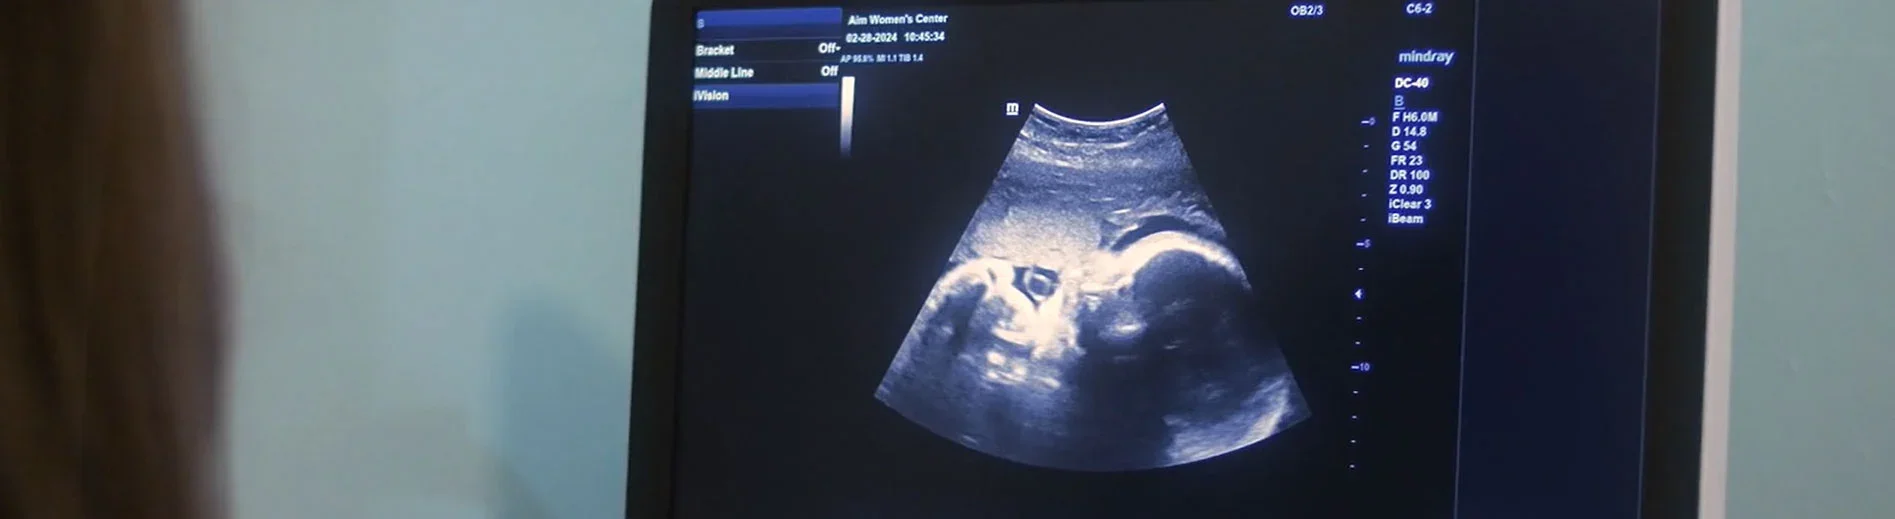

A fetal ultrasound (sonogram) is an imaging technique that uses high-frequency sound waves to produce images of the inside of your uterus. There are no known harmful effects that occur from an ultrasound procedure.

Our technician applies a gel-like substance to your abdomen. The gel helps transmit sound waves. A hand-held device called a transducer is rubbed over the gel to record the echoes of the sound waves it picks up.

The sound waves reflected off your bones and other tissues are converted into images on a computer monitor.